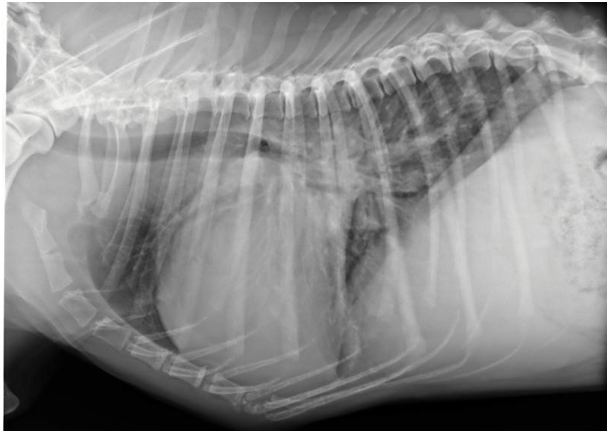

Die Krankheit „Dilatative Cardio Myopathie“ hat sich bereits vor vielen Jahren geäußert bei unserem Dobermann. Als ein Dobermann plötzlich starb wurde damals oft gesprochen von „Sudden Death“. Ebenfalls konnten Tierärzte mit klinischer Untersuchung, Röntgenbild und Elektrokardiogram Herzversagen bestätigen beim Dobermann mit reduzierter Kondition. Mit mikroskopischer Untersuchung konnte man Narbe Gewebe zwischen noch gesunde Herzmuskelzellen feststellen.

Röntgenbild vom Dobermann mit vergrößertem Herz und Wasser in der Lunge